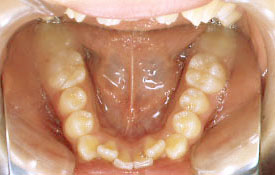

インビザラインの治療例:CASE-1

| プロフィール | 42歳 女性 |

| 所見 | 他院で行われた矯正歯科治療後の後戻りに悩まれて来院されました。 アイライナーの装着は、1日平均20時間ほどでした。 |